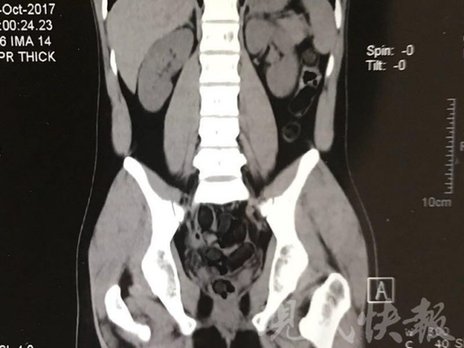

由于毒品在體內(nèi)一旦泄露有可能致命,警方第一時間將阿永帶到醫(yī)院進行檢查。CT 掃描的結(jié)果顯示,阿永體內(nèi)布滿了密密麻麻的白色圓柱狀固體,就像一粒粒的蠶蛹。在南京市公安局鼓樓分局二板橋派出所,阿永分四次排出了毒品,毛重369.99克。經(jīng)訊問,阿永交代了自己全部的犯罪事實。目前,阿永已被刑事拘留。